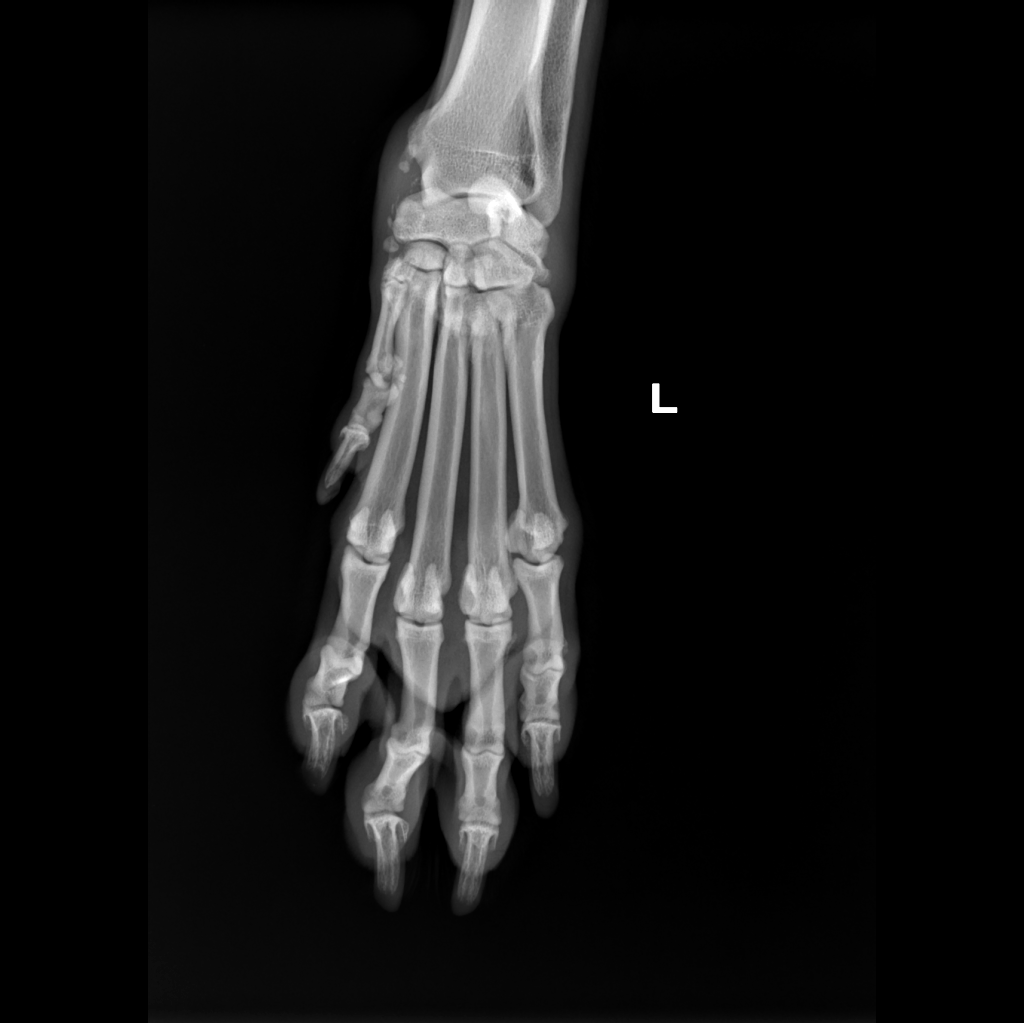

x-ray with awake patient was performed on forelimb (medio-lateral view of elbows and dorso-palmar view of carpus) and latero-lateral view of thoracic and lumbar vertebrae.

and degenerative changed on medial aspect of left carpus (in differential diagnosis: Abductor Pollicis Tenosynovitis vs peri-articular mineralization of unknown etiology)